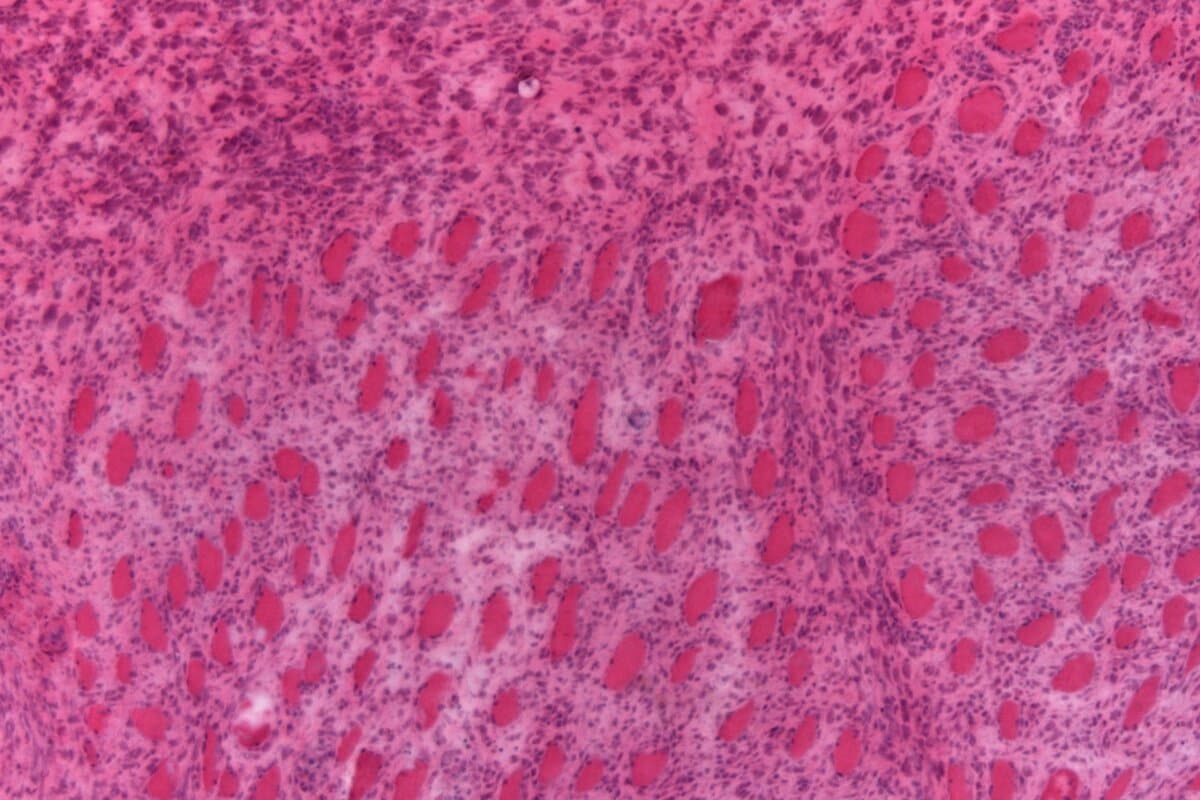

Die frühe rheumatoide Arthritis muss so rasch wie möglich in Remission gebracht werden – das fordern die rheumatologischen Fachgesellschaften. Doch welche Strategie dafür am besten geeignet ist, bleibt unklar. Eine Analyse deutet darauf hin, dass Gelenkspritzen kombiniert mit einer Tripletherapie Vorteile bieten könnten.